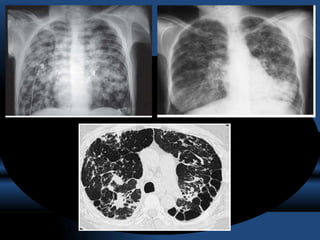

RADIOGRAFIA.

• La sensibilidad de la radiografía de tórax varia de un 45 a un 70% en relación

al diagnóstico de las bronquiectasias.

• Las bronquiectasias producen engrosamiento de la pared bronquial originando

el signo “ en raíles de tren” (tram lines).

• Acúmulo de secreciones a nivel bronquial ,“signos del dedo de guante”

• Imágenes quísticas, a veces incluso con nivel hidroaéreo y opacidades

anulares.

• El apelotonamiento de bronquiectasias quísticas en una zona pueden dar una

imagen similar a la del pulmón en panal.

• Atelectasias por obstrucción por tapones mucosos

TOMOGRAFIA COMPUTARIZADA DE ALTA RESOLUCION

= GOLD STANDARD